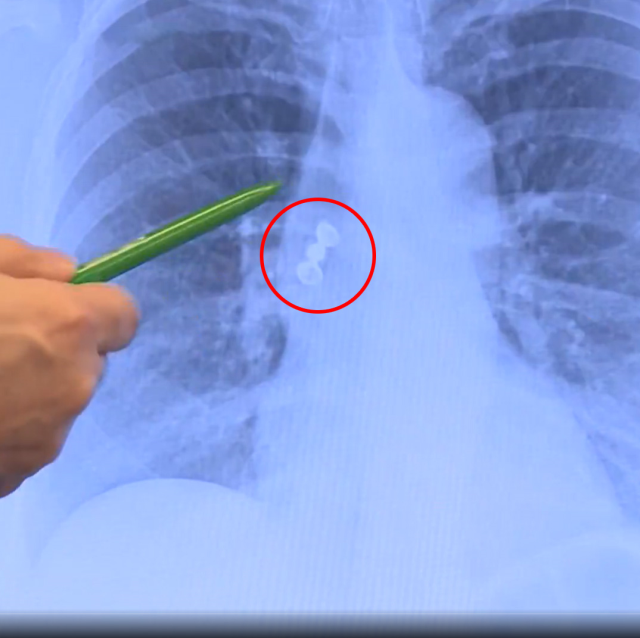

RÖNTGEN SONUCU DOKTORLARI DA ŞAŞIRTTIHastanede çekilen akciğer grafisi, olayın seyrini değiştirdi. Üç dişten oluşan kaplama köprünün akciğere kaçtığı belirlendi. Doktorlar, solunum yollarını tıkama riski bulunan durum nedeniyle hastayı hemen tedavi altına aldı. Kaplama diş, bronkoskopi yöntemiyle başarılı şekilde çıkarıldı.

"ERİŞKİNLERDE ÇOK NADİR GÖRÜLÜR"TRT Haber'e konuşan Göğüs Hastalıkları Uzmanı Prof. Dr. Levent Alpay, akciğer filminde kaplama köprünün aspire edildiğini tespit ettiklerini ve hastayı hemen yatırdıklarını söyledi. Alpay, bu tür vakaların genellikle çocuklarda görüldüğünü, erişkinlerde ise oldukça nadir rastlandığını belirtti.